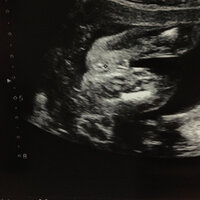

妊娠7ヶ月 エコー写真でここまで分かる ついに性別判明 25歳はじめての妊娠 8 18年3月21日 エキサイトニュース 2 3

エコー写真 性別の見分け方 男の子女の子別エコー 妊娠週まとめてみました ママびよりウェブ

ベビーナブ 妊娠初期12週で性別が判明 実際のエコー写真 正面 横 下 くまよblog

19週で性別判明 男の子と確定したエコー写真 ぽむらいふ おうちと暮らしを楽しむ